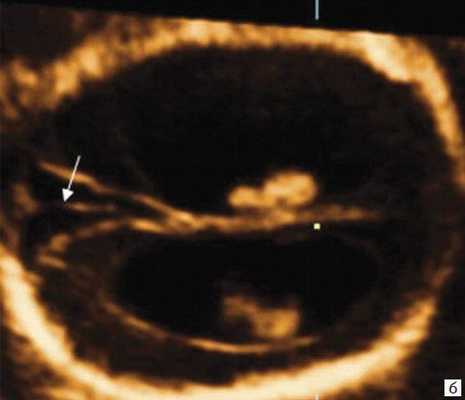

Анализ сохраненных трехмерных изображений позволил получить более детальные характеристики структур мозга плодов с РЭС. На среднесагиттальном срезе в наблюдениях 1, 2 и 4 (в наблюдении 3 получить качественно этот срез не удалось) отмечено наличие атипичной полукруглой формы шатра (fastigium) 4-го желудочка, гипоэхогенная структура мозжечка с контрастирующим наружным контуром (рис. 3). При этом в первых трех наблюдениях отмечено полное отсутствие структур червя, тогда как в наблюдении 4 по контуру 4-го желудочка выявлены гиперэхогенные структуры, расцененные как передние отделы червя. Наличие передних отделов червя отражает и ряд послойных срезов в режиме TUI (рис. 4). У плода в наблюдении 4 также обращает на себя внимание относительное расширение надмозжечковой цистерны, с линейными структурами, при нормальной ориентации намета мозжечка (рис. 4).

а) Наблюдение 2, 3D. На эхограмме: 1 - боковой желудочек, 3v - 3-й желудочек, стрелки - контур мозжечка, пунктирная линия - шатер.

б) Наблюдение 4. На эхограмме: М - мозжечок.